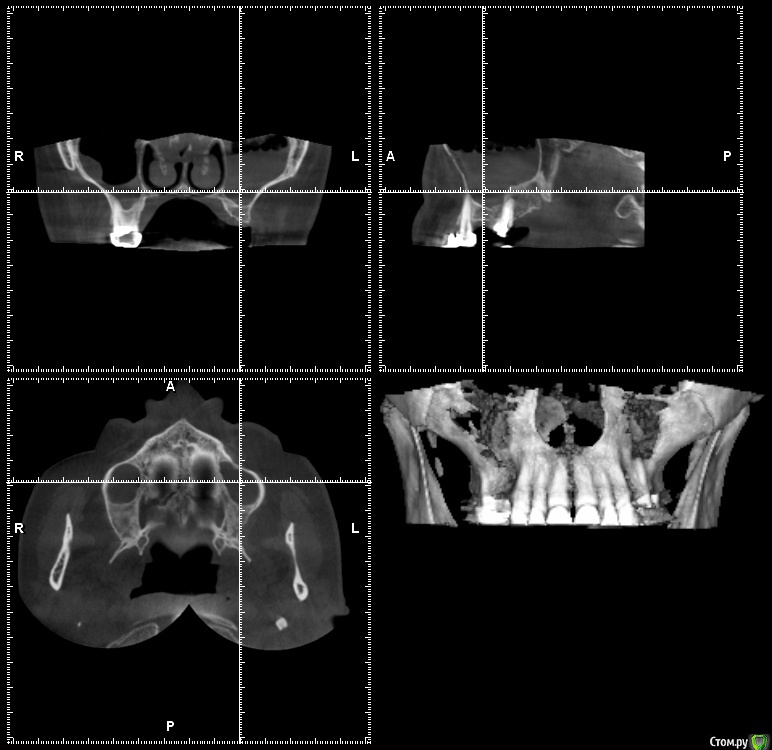

gum Опубликовано 15 сентября, 2015 Поделиться Опубликовано 15 сентября, 2015 Коллеги здравствуйте. У пациентки планируется двусторонний синус лифт, но по кт в пазухе проблемы. Клинически пациентка никогда не жаловалась. Отправил к ЛОРу было проведено терапевтическое лечение. ЛОР сказала, что не видит преград для операции. Соустьев на КТ не видно. Отправлять к другому ЛОРу? и вообще как при таких изменениях в пазухе проводить операцию. Подскажите какую литературу лучше почитать, Ссылка на комментарий

Bier Опубликовано 16 сентября, 2015 Поделиться Опубликовано 16 сентября, 2015 надо делать КТ на котором видно соустье + на зубе периодонтит? не видно из-за сеток на снимке. 1 Ссылка на комментарий

major Опубликовано 16 сентября, 2015 Поделиться Опубликовано 16 сентября, 2015 Да после лечения ЛОРаТогда да, другой оториноларинголог вам в помощь, с новым КТ. И действительно, на первом снимке, на зубе периапикальные изменения? или срез так расположен? Ссылка на комментарий

gum Опубликовано 28 сентября, 2015 Автор Поделиться Опубликовано 28 сентября, 2015 Пациентка принесла новый 3D. С пазухами. Слева сообщение с полостью носа есть, а справа по снимку оно не прослеживается.. Можно ли делать открытый синус лифт или к другому ЛОРу отправлять Ссылка на комментарий

Bier Опубликовано 28 сентября, 2015 Поделиться Опубликовано 28 сентября, 2015 а периодонтит? )Если кроме этого утолщения больше ничего нет - можно оперировать. 1 Ссылка на комментарий